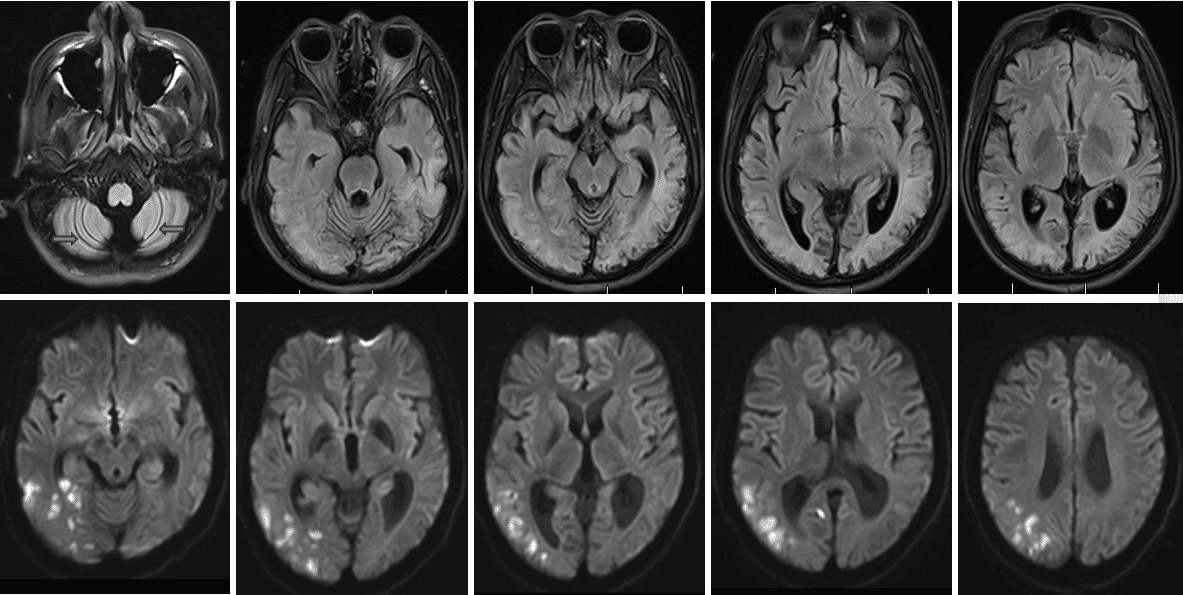

图1 ,头MR(Flair及DWI序列 2023-8-12)提示双侧小脑脑沟增深,与18岁成人脑组织影像不符;另外,弥散像可见右侧颞顶枕叶点片状稍高信号影;乳酸:12.56mmol/L,↑;